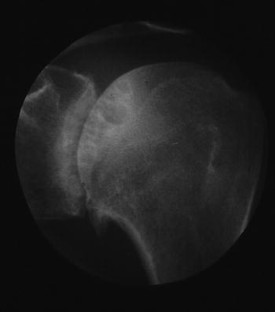

SAPHO: syndrome or concept? Imaging findings

The SAPHO syndrome was a term coined to include a variety of musculoskeletal disorders associated with skin conditions, mainly palmoplantar pustulosis and acne conglobata. It is more correctly a spectrum which includes the following: skin lesions, osteoarticular manifestations of synovitis hyperostosis and osteitis affecting particular target sites, and·a clinical course marked by relapses and remissions. The major sites of involvement are the anterior chest wall, the spine, long bones, flat bones, and large and small joints. The distribution and severity of involvement varies from the adult to the pediatric form of chronic recurrent multifocal osteomyelitis (CRMO). The diagnosis of SAPHO syndrome is not difficult when the typical osteoarticular lesions are located in characteristic target sites. The diagnosis is more difficult if atypical sites are involved and there is no skin disease.